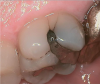

Fig 3. Occlusal view of the tooth before the restoration.

Fig 4. Palatal view of the tooth before the restoration.

Figure 4